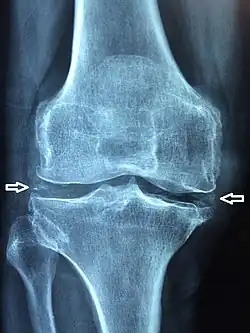

X-ray, CT, or other imaging usually shows accumulation of calcium within the joint cartilage, known as chondrocalcinosis. There can also be findings of osteoarthritis.[5][4] The white blood cell count is often raised.[4]

Medical imaging, consisting of x-ray, CT, MRI, or ultrasound may detect chondrocalcinosis within the affected joint, indicating a substantial amount of calcium crystal deposition within the cartilage or ligaments.[2] Ultrasound is a reliable method to diagnose CPPD.[8] Using ultrasound, chondrocalcinosis may be depicted as echogenic foci with no acoustic shadow within the hyaline cartilage[9] or fibrocartilage.[8] By x-ray, CPPD can appear similar to other diseases such as ankylosing spondylitis and gout.[2][4]

Calcium pyrophosphate dihydrate crystals are associated with a range of clinical syndromes, which have been given various names, based upon which clinical symptoms or radiographic findings are most prominent.[13] A task force of the European League Against Rheumatism (EULAR) made recommendations on preferred terminology.[6] Accordingly, calcium pyrophosphate deposition (CPPD) is an umbrella term for the various clinical subsets, whose naming reflects an emphasis on particular features. For example, pseudogout refers to the acute symptoms of joint inflammation or synovitis: red, tender, and swollen joints that may resemble gouty arthritis (a similar condition in which monosodium urate crystals are deposited within the joints). Chondrocalcinosis,[2][4] on the other hand, refers to the radiographic evidence of calcification in hyaline and/or fibrocartilage. "Osteoarthritis (OA) with CPPD" reflects a situation where osteoarthritis features are the most apparent. Pyrophosphate arthropathy refers to several of these situations.[17]